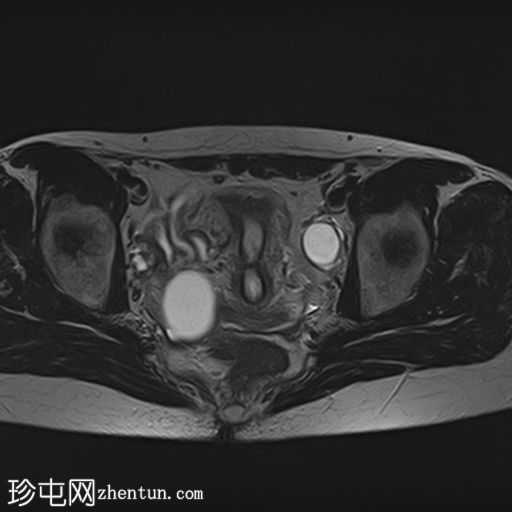

轴向

T2

4.jpg

已确诊3例卵巢囊肿:

右侧卵巢出血性囊肿,T1成像呈中等信号,T2成像呈高信号,伴有薄内部分隔

左侧卵巢出血性囊肿,信号特征与右侧囊肿相似

左侧单纯性卵巢旁囊肿,T1成像呈低信号,T2成像呈高信号

此外,所有囊肿均未显示弥散受限或实性成分强化。

所有囊肿均仅显示薄层外周壁强化。

道格拉斯囊右侧可见轻度积液。

本例卵巢囊肿呈中等 T1 信号,类似于肌肉信号,T2 信号高,伴有薄内隔和外周壁强化。但无内部强化或弥散受限。STIR 序列显示与 T2 一致的信号,无任何脂肪成分。该表现提示卵巢出血性囊肿处于早期或消退期。

此外,左侧卵巢旁囊肿外观简单,T1 信号低,T2 信号高。